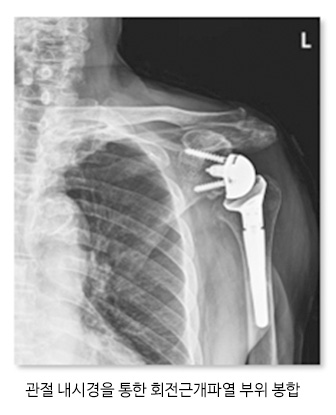

회전근개 파열은 조기에 진단을 하여 치료하는게 중요합니다. 힘줄이 완전히 끊어지지 않았다면 약물치료, 물리치료, 체외충격파치료 등 활용하여 치료를 시행하고 힘줄이 완전히 끊어 졌다면 관절 내시경 장비를 통하여 회전근개를 봉합하는 수술을 진행하고 끊어진 상태로 오래 방치했거나 피열 정도가 심해 봉합이 어려운 경우 인공관절 수술을 하기도 합니다.

관절내시경